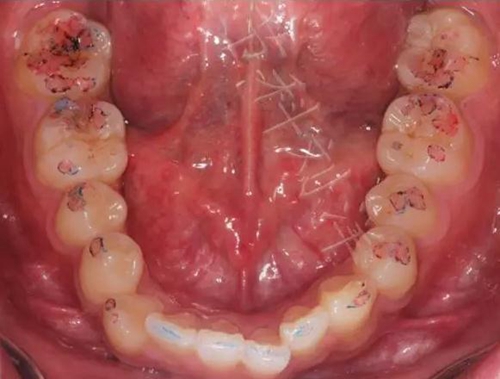

02,功能運動咬合點

①咬住200微米藍色咬合紙,前后左右磨,

▲ 圖5:200μm咬合紙

▲圖6:200µm 功能運動